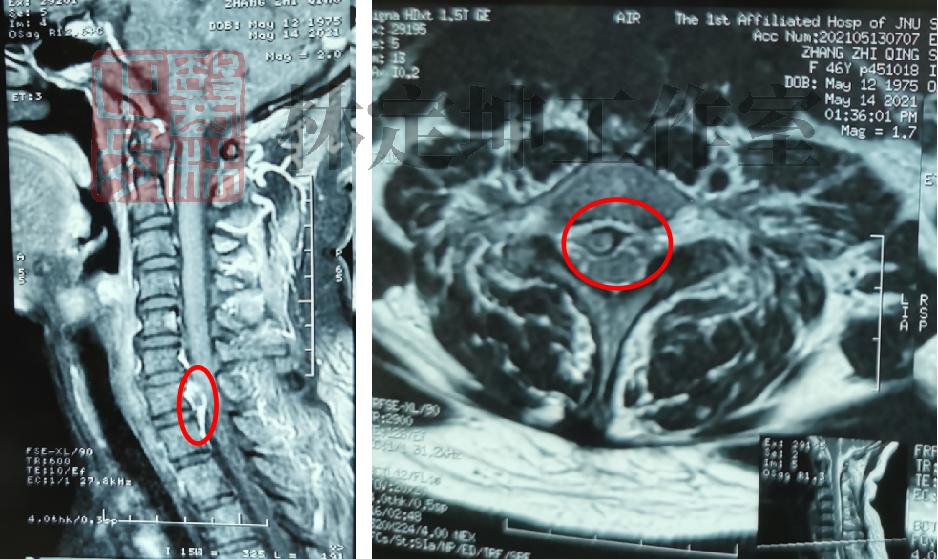

核磁共振检查显示,李女士的颈椎存在椎间盘突出的情况,导致颈椎C8的神经根受压迫,从而引起了该节段神经根的后支分布范围出现疼痛症状,也就是李女士现在的背部痛症。

(核磁共振显示李女士颈椎存在椎间盘突出,颈髓受压的情况)